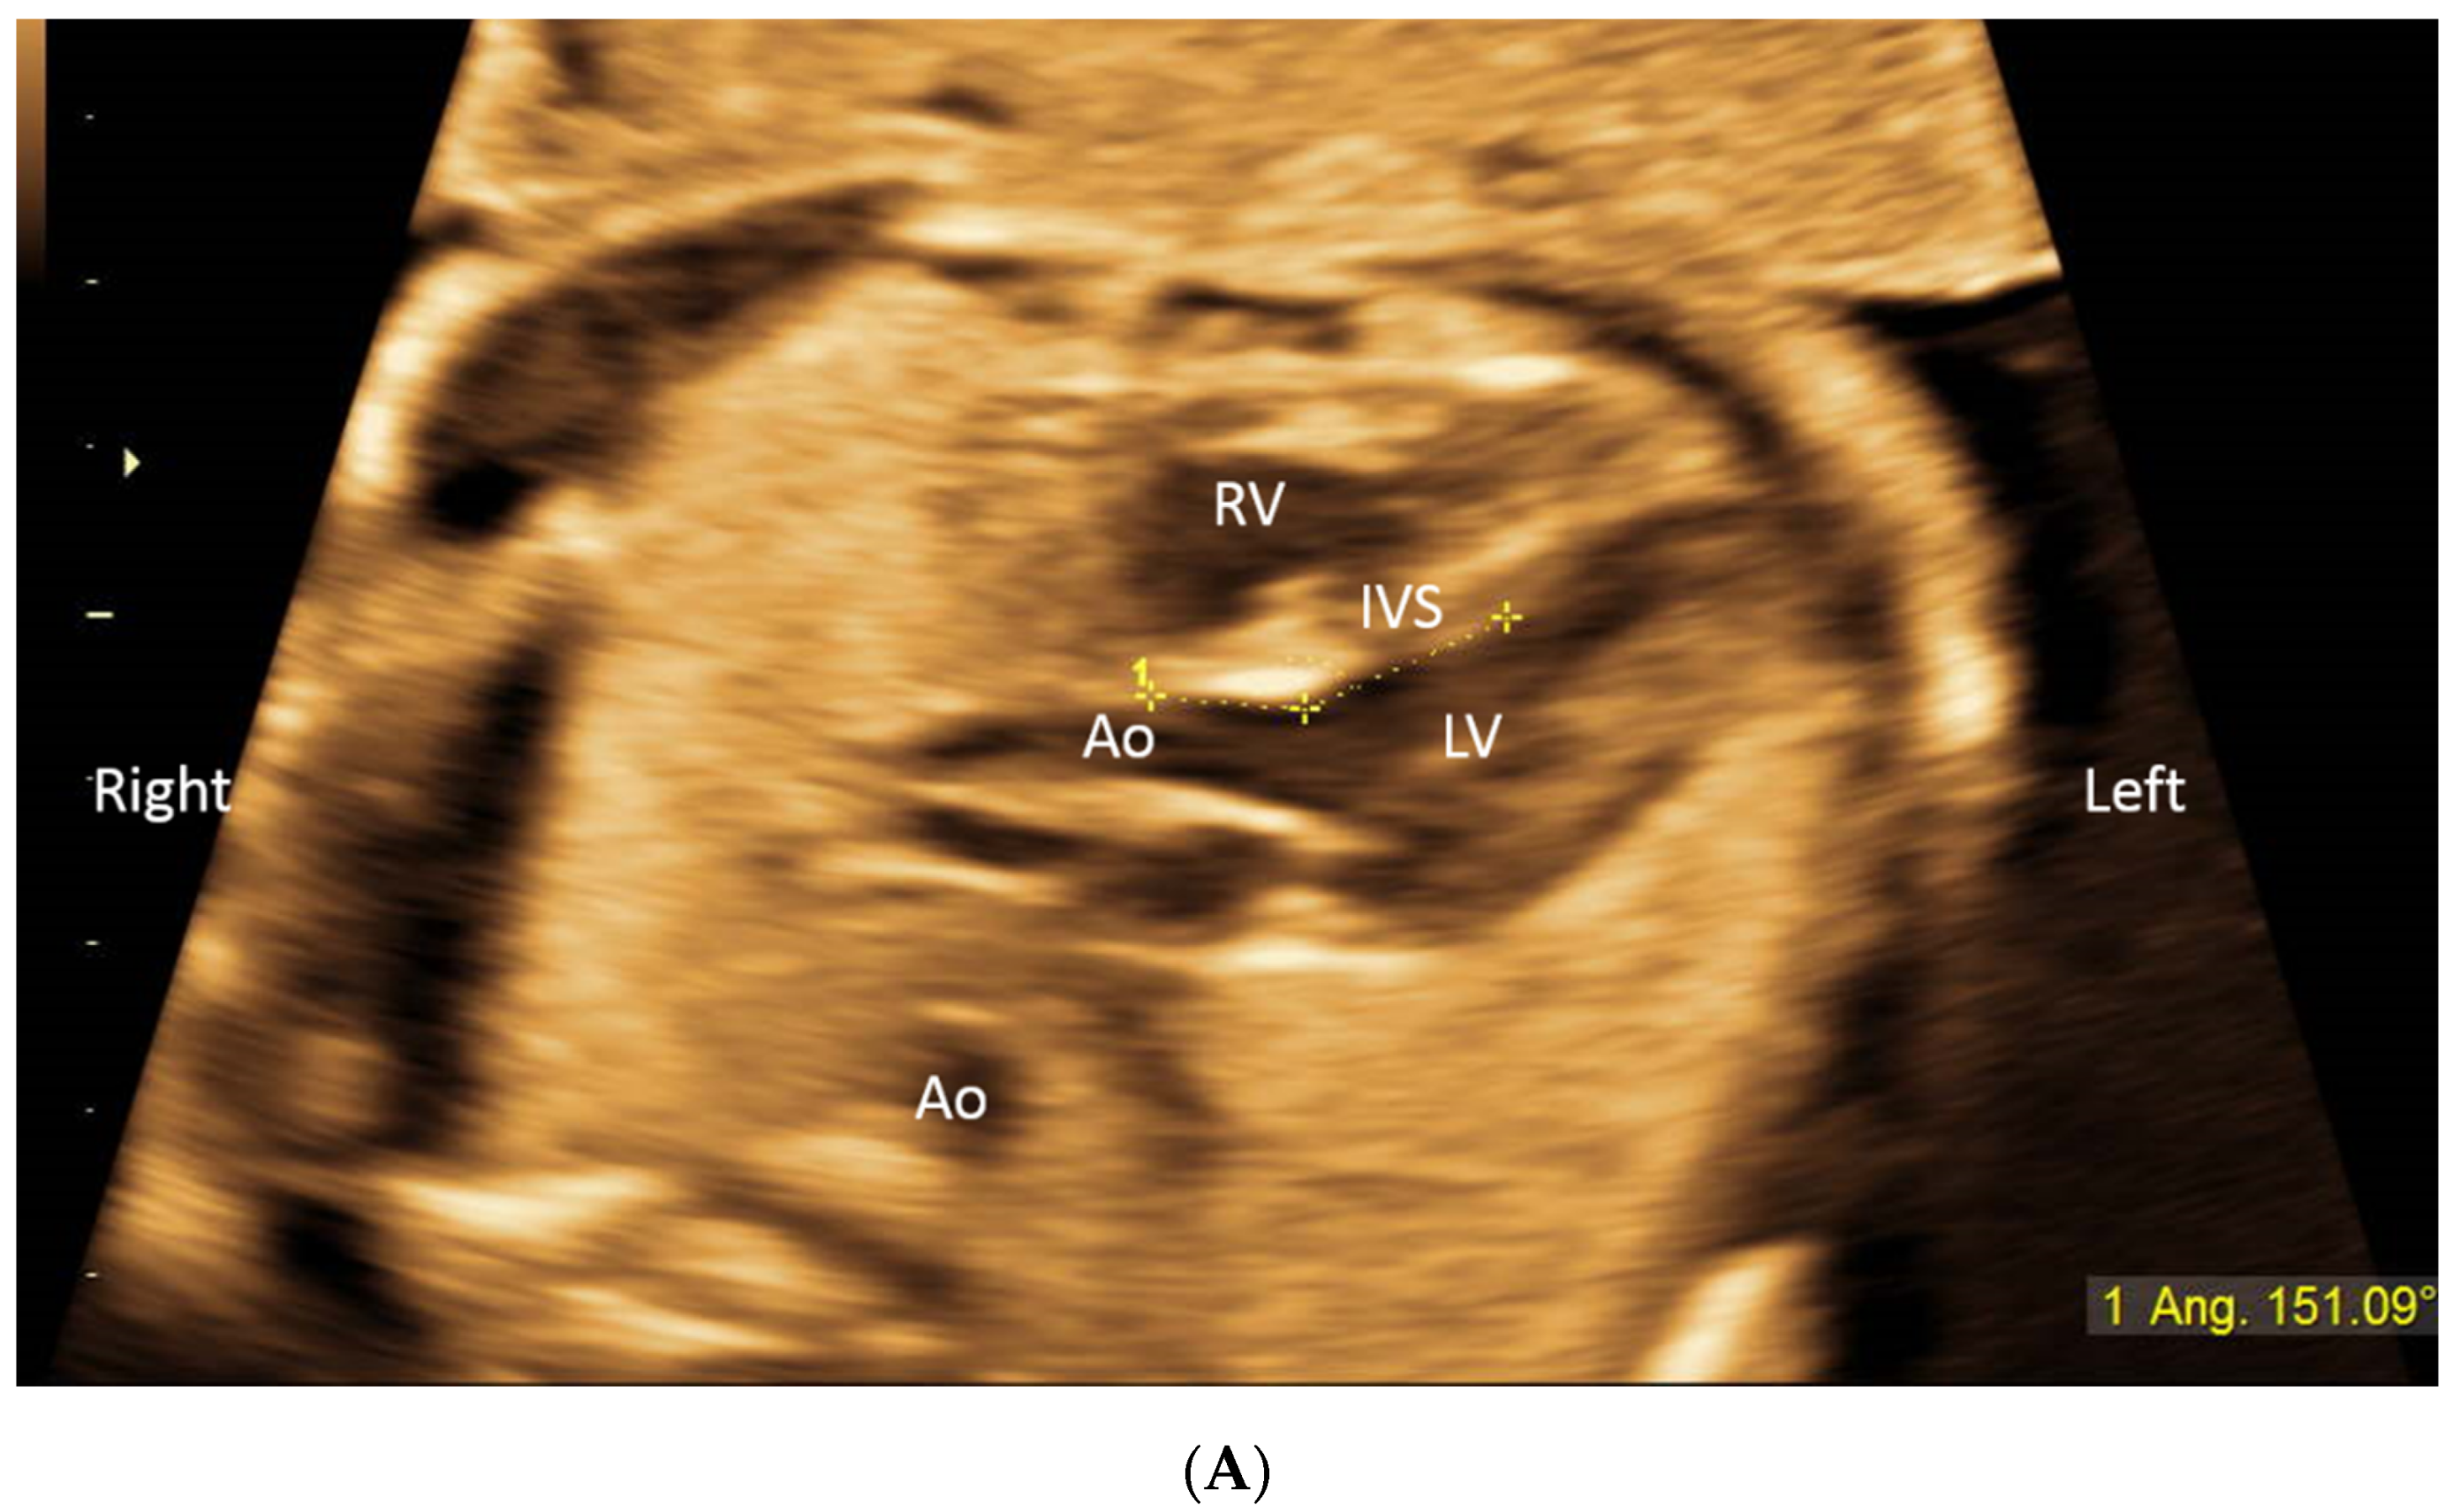

2. Methods

3. Results